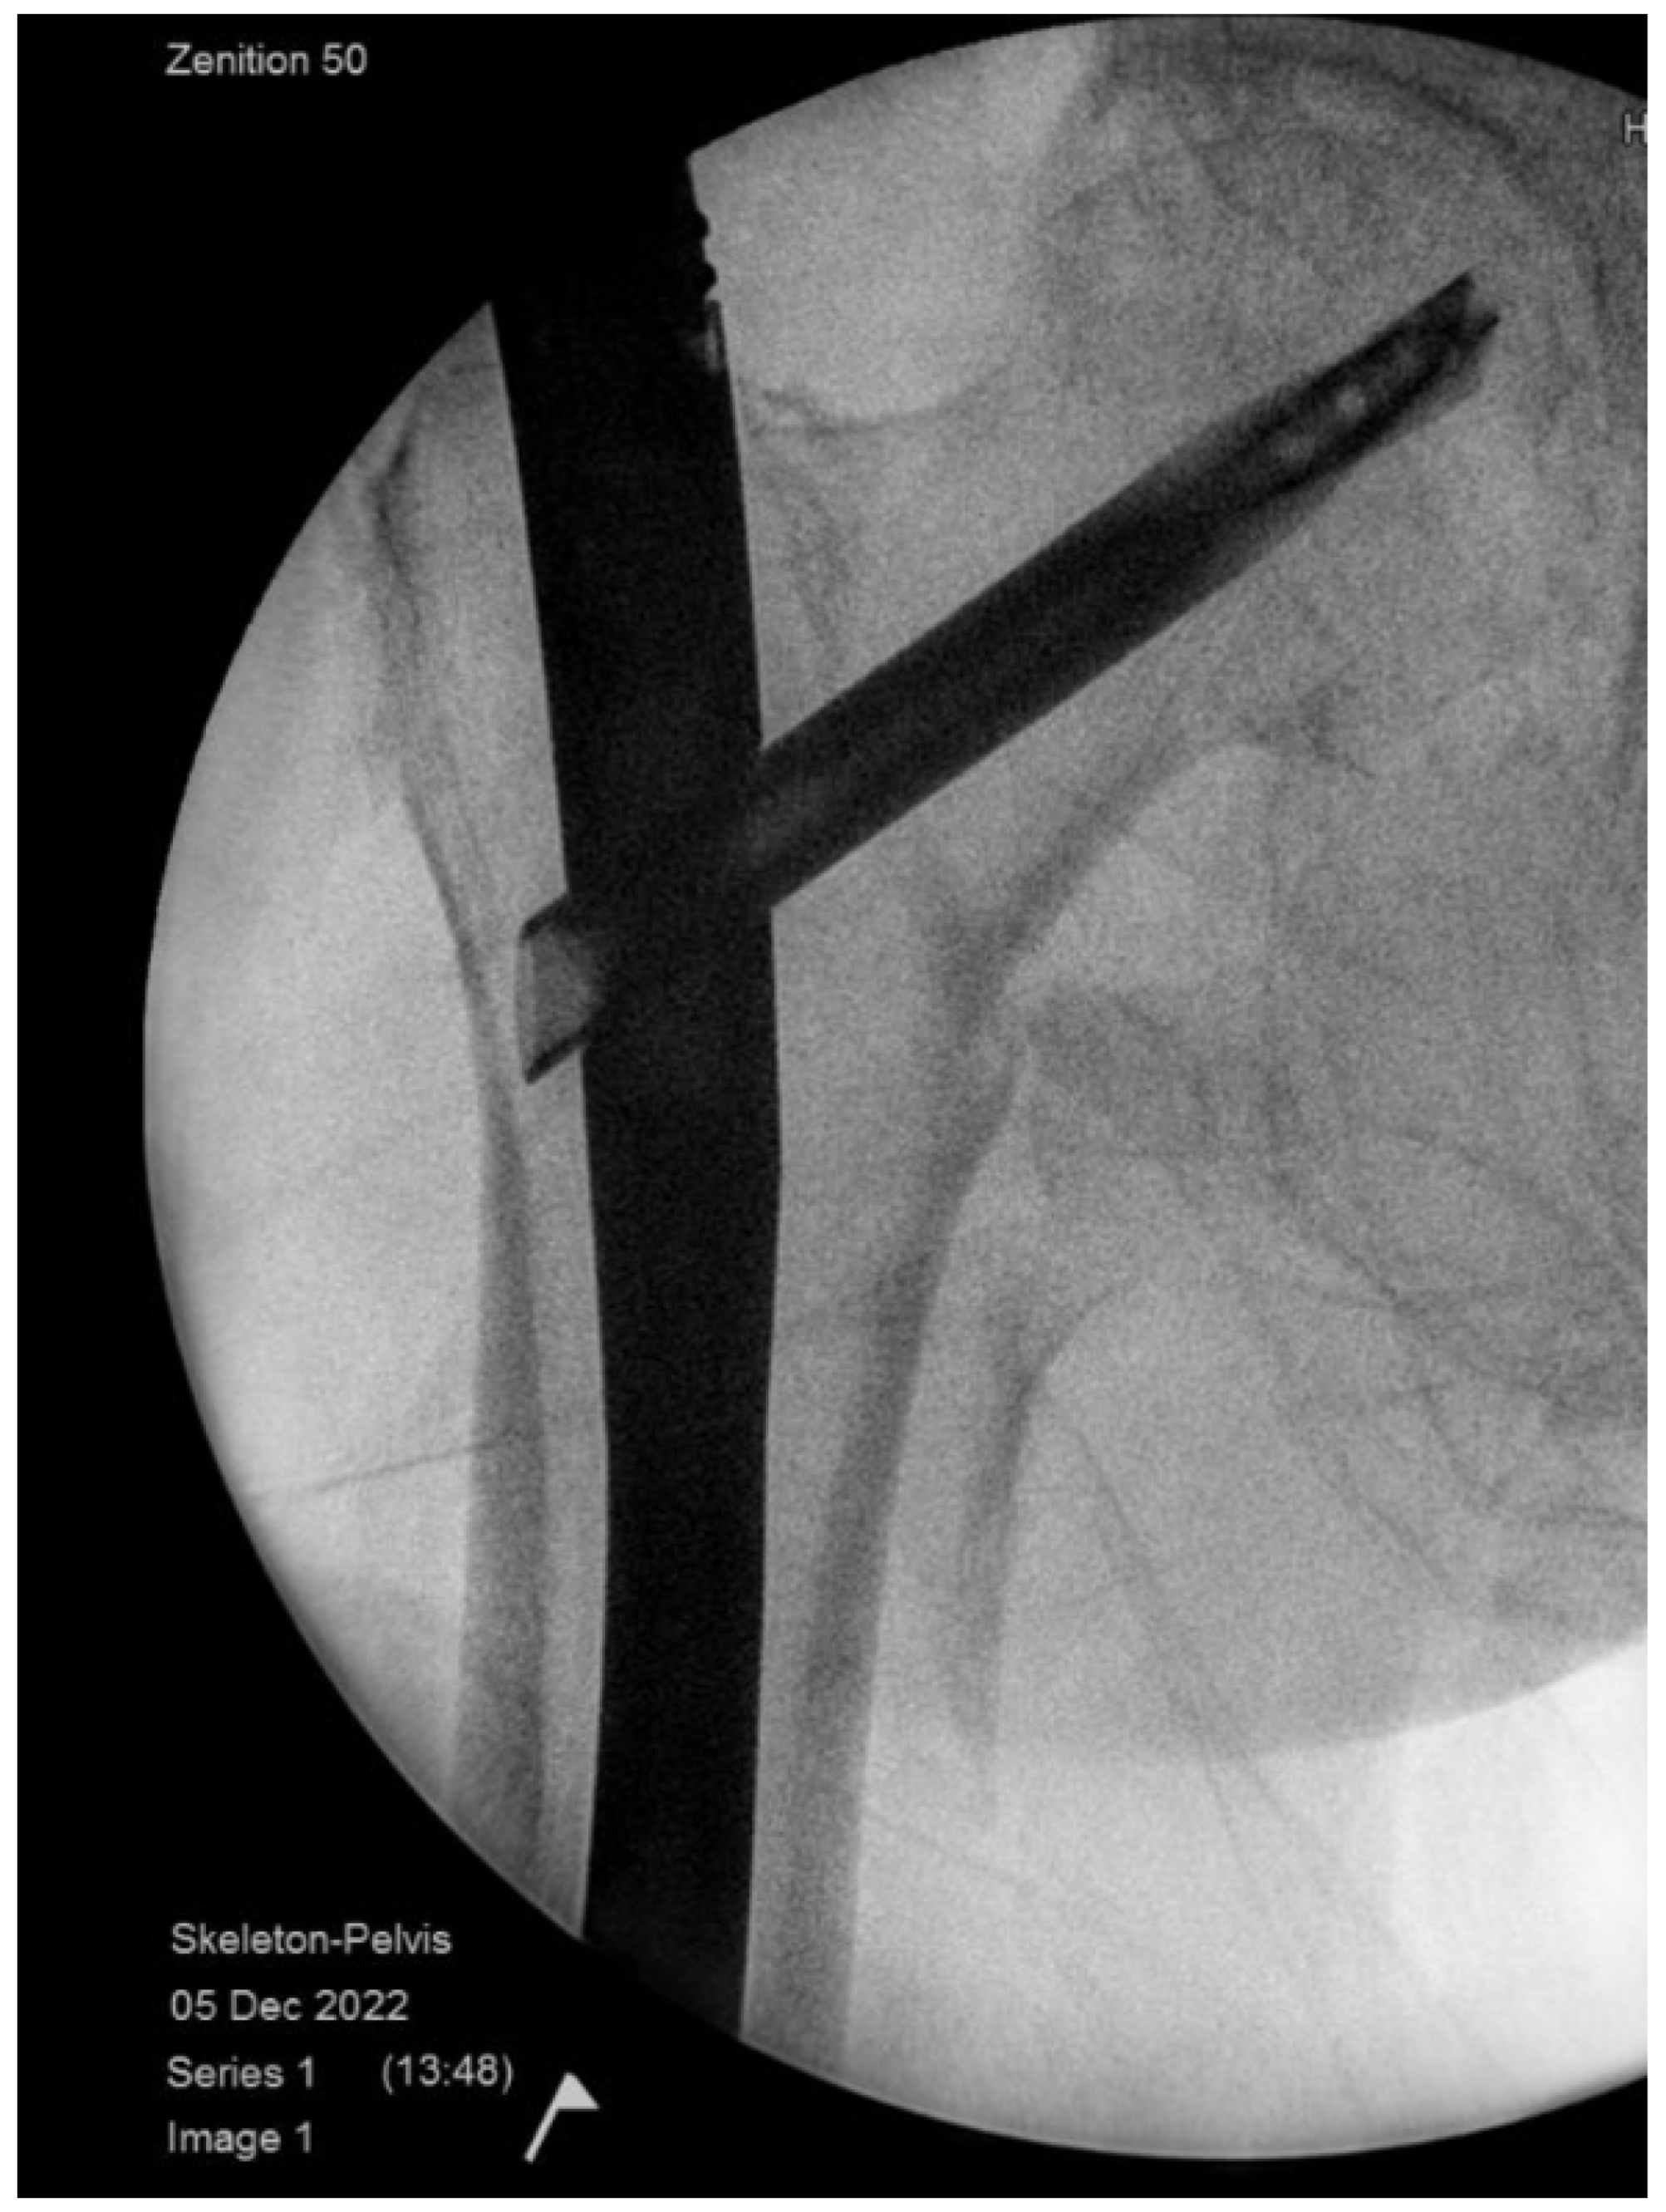

2.7.1. Case 1—Failure to Reduce Anatomically